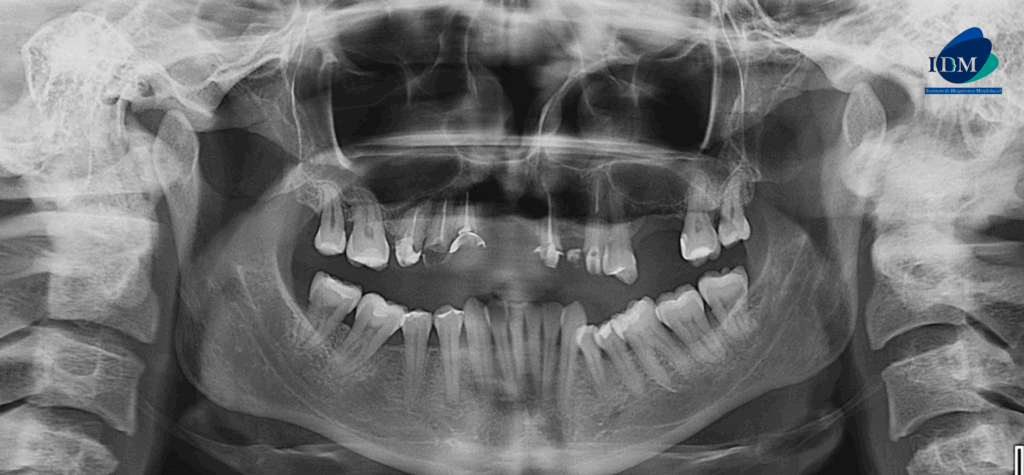

En la radiografía panorámica (Figura 1), se aprecia piezas dentarias con material de obturación, además se evidencia imagen radiopaca definida a nivel apical de pieza 21.

Radiografia Panorámica